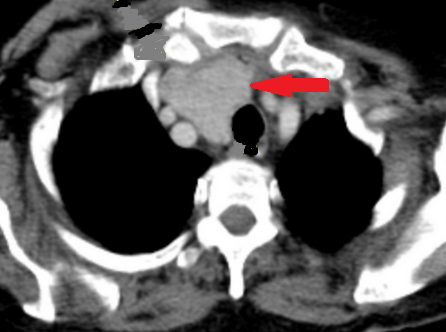

CT. Σημαντικό αιμάτωμα εκτεινόμενο στον προκυστικό χώρο (Ευγενική παραχώρηση Dr. V. Penopoulos).